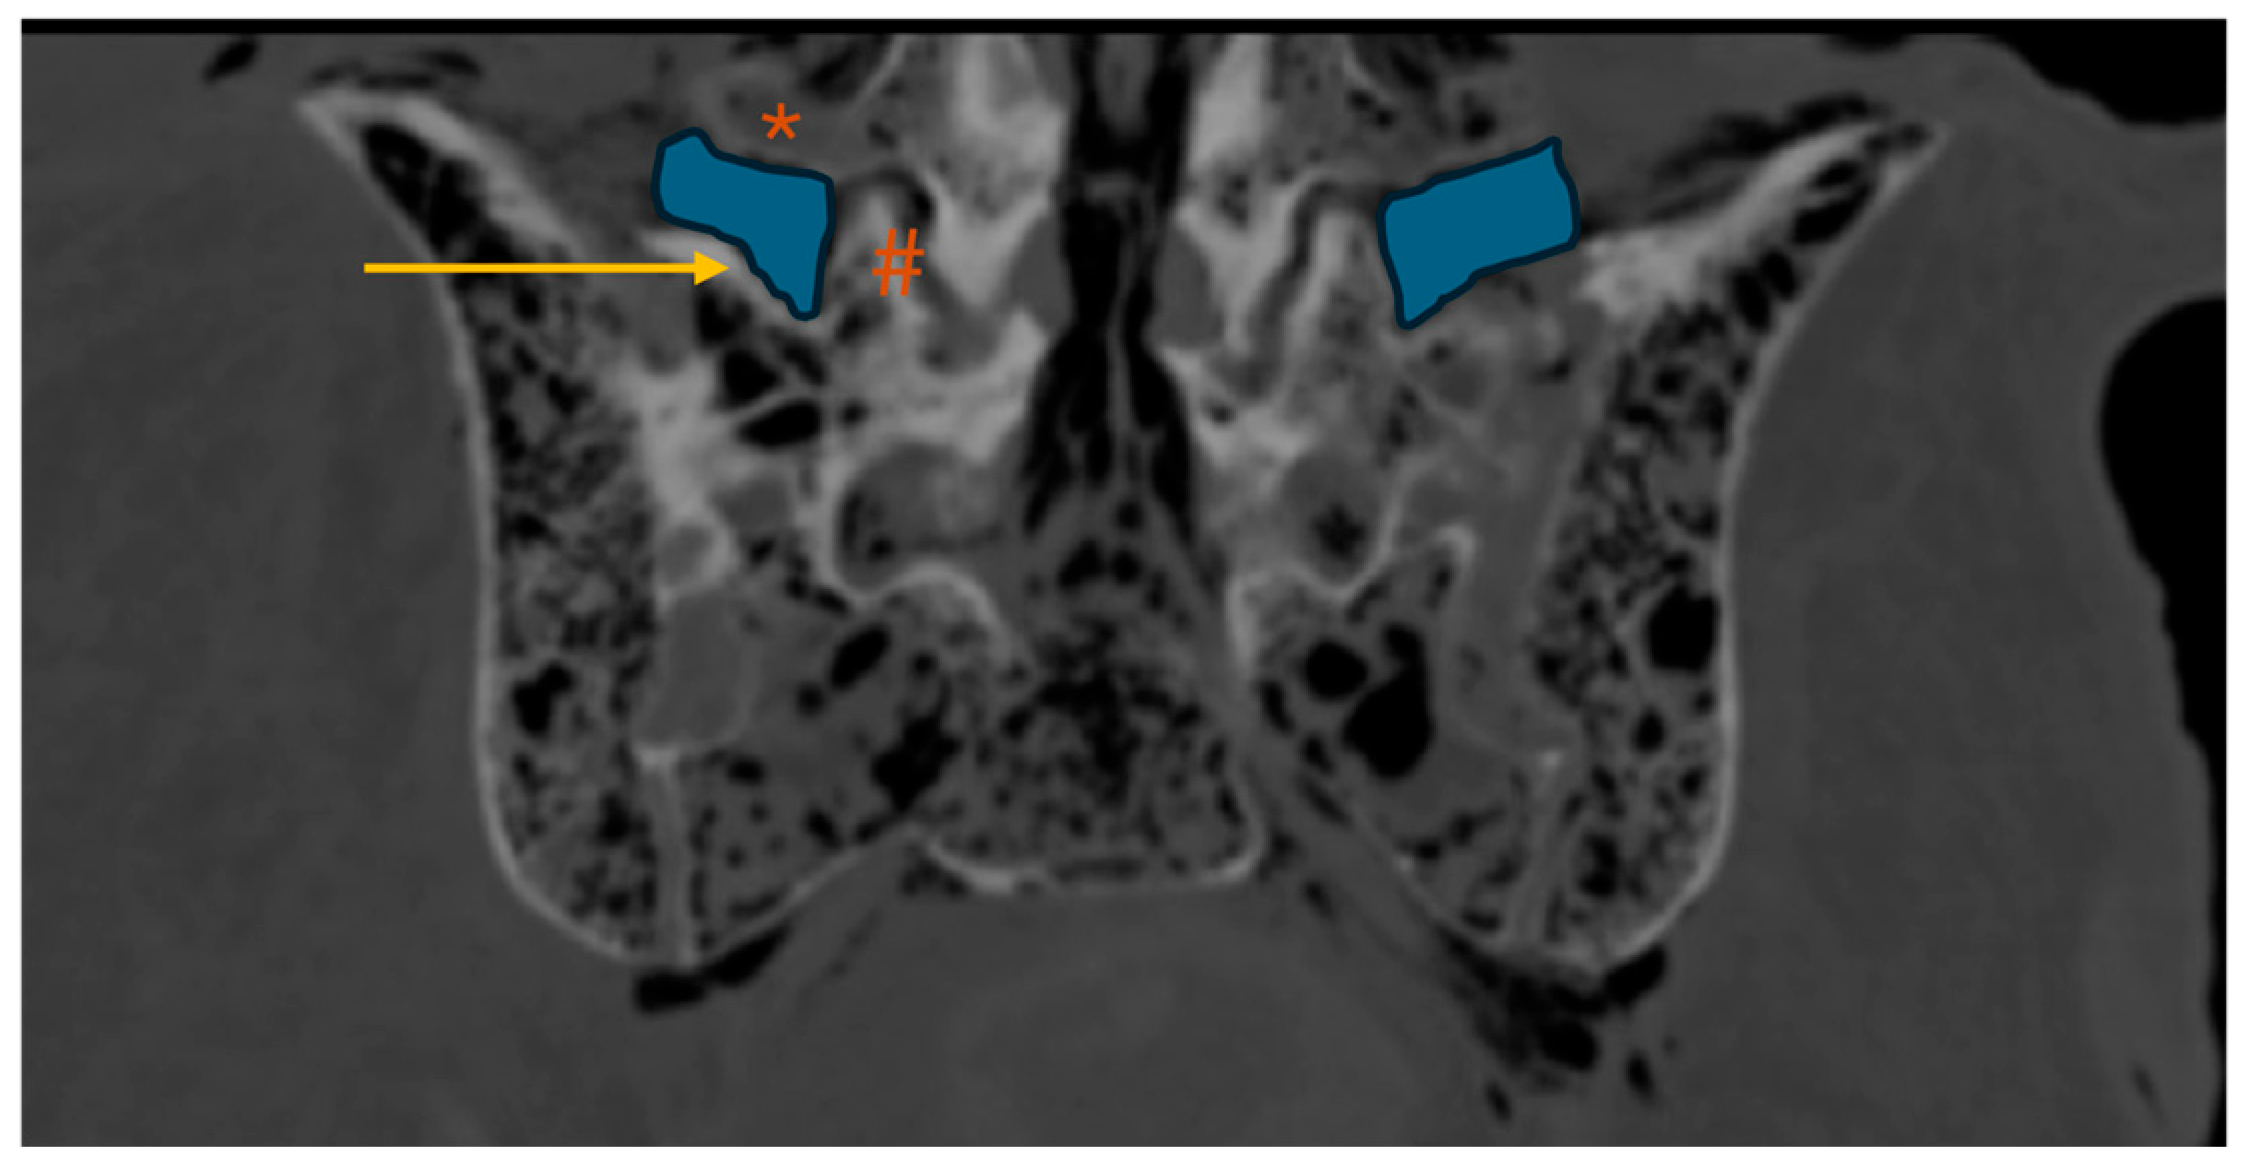

• MaxTP-sacrum and minTP-sacrum: maximum and minimum distance from the inferior border of the L5 TP to the superior border of the sacral ala, respectively, (coronal plane intersecting the L5 TP center; Figure 3)

The maxTP-sacrum distance (Figure 3) was 11.1(4.0)mm, consistently located in the second quarter of the L5 TP (from its base). The mean minTP-sacrum distance (Figure 3) was 5.6±2.9mm, always near the L5 TP tip. No statistically significant differences were observed between nondysmorphic and dysmorphic upper sacral morphology (p=0.662 and p=0.498, respectively).

Figure 3. Lumbar spine CT – coronal plane; *: L5 transverse process; arrow: sacral ala; dotted yellow line: maxTP-sacrum (maximum distance from the inferior border of the L5 transverse process to the superior border of the sacral ala); solid yellow line: minTP-sacrum (minimum distance from the inferior border of the L5 transverse process to the superior border of the sacral ala).